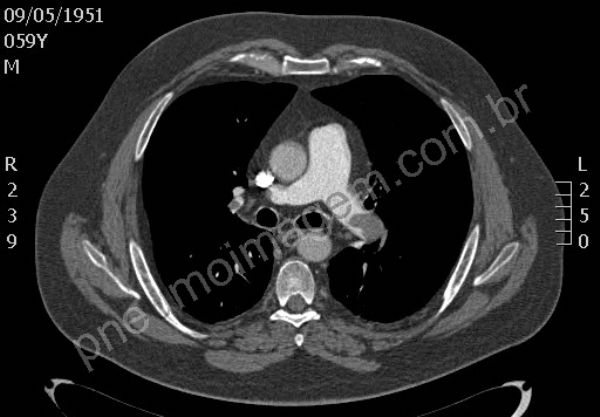

Tromboembolia pulmonar (TEP). Na sequência tomográfica observam-se trombos localizados no tronco da artéria pulmonar e nos principais ramos segmentares à esquerda. Os trombos na bifurcação do tronco pulmonar à direita estendem-se para ramos segmentares do lobo superior, para a interlobar descendente e ramos segmentares do lobo médio. O paciente apresentava também trombose venosa profunda (TVP) na veia femural esquerda, fator de risco importante para TEP. Chaves: tromboembolismo, embolia pulmonar.

Pulmonary thromboembolism (PTE). In tomographic sequence are observed thrombi located in the main pulmonary artery and major segmentary branches left. Thrombi in the bifurcation of the pulmonary trunk right extend to segmentary branches of the upper lobe, extend to descending interlobar and segmentary branches of the middle lobe. The patient also presented deep vein thrombosis (DVT) in the left femoral vein, an important risk factor for PE. Keys: pulmonary embolism (PE).